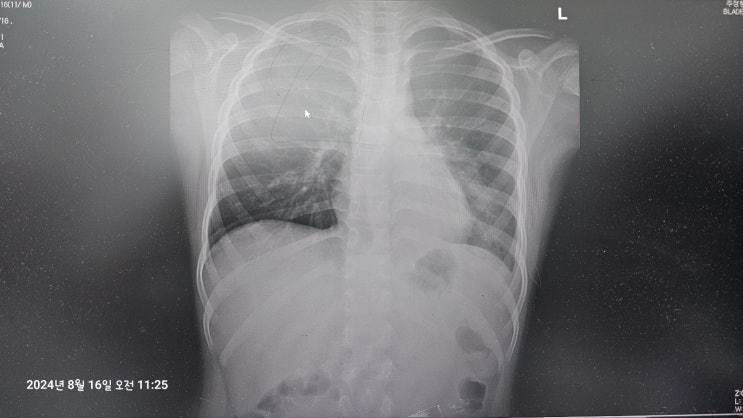

마이코플라즈마 폐렴에서 약물 복용 부작용으로 인한 스티븐 존슨 증후군 희귀 난치병 병원 진료 및 회복 기간

안녕하세요. 가을철 쭈꾸미 갑오징어 낚시 준비에 여념이 없는 카리스마 욱입니다. 거기다 최근 겹친 아들...

마이코플라즈마 폐렴 확인 및 응급실 치료 가능한 병원 찾는 방법과 입원 없이 자가 치료 후기 회복 기간

안녕하세요. 살살 불어오는 가을바람에 러닝하고 온 카리스마 욱입니다. 오늘은 낚시 이야기가 아닌 최근 ...